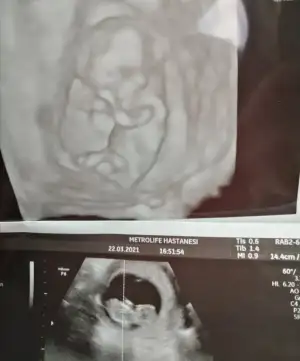

herkes sağolsun gerçekten sıkıldıkça insan buraya giriyor fikir alıyorErkek sankiEki Görüntüle 2807800 Kızlar bizede tahmin de bulunur musunuz

Doktorumuzda çıkıntıya göre erkek gibi ama kordonda olabilir demişti netleşince yazarımErkek sanki

Merhaba, bebeğin cinsiyeti için erkek olabilir demiştiniz ve doğru tahmin etmişsiniz. Tahmininiz için teşekkür ediyorum :)En iyi 11 12 13 haftalar olmalı

Evet net kız görünüyorMerhaba arkadaşlar 12+4 tahminler var mı dr um %80 Kiz dedi

Kız sanki